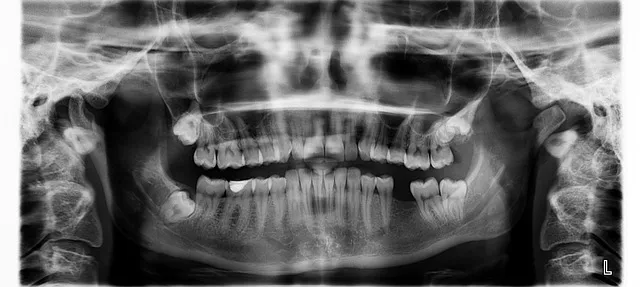

3. 정기적인 치과 검진과 치료

노인들은 정기적인 치과 검진과 치료를 받아야 합니다. 치과 의사는 치아와 구강 건강을 평가하고 필요한 치료를 제공할 수 있습니다.

- 구강 질환의 조기 발견과 예방에 도움을 줍니다.

- 치아와 구강 건강의 유지에 도움을 줍니다.

- 필요한 경우 치아 추출이나 치아 보철 등의 치료를 제공할 수 있습니다.